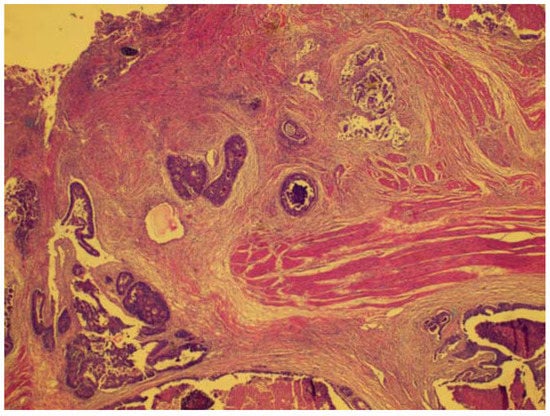

Figure 1. A rectal wall with ulcerated mucosa (top) and tumor islands infiltrating into the muscular propria layer.

The surgical samples were fixed with 10% formalin and embedded in paraffin. The tissue slices were stained with hematoxylin and eosin. The hematoxylin-and-eosin-stained slices were evaluated by an experienced colorectal cancer pathologist. The pathological determination of the T and N stages was used as the reference standard according to the guidelines of the American Joint Committee on Cancer (AJCC).